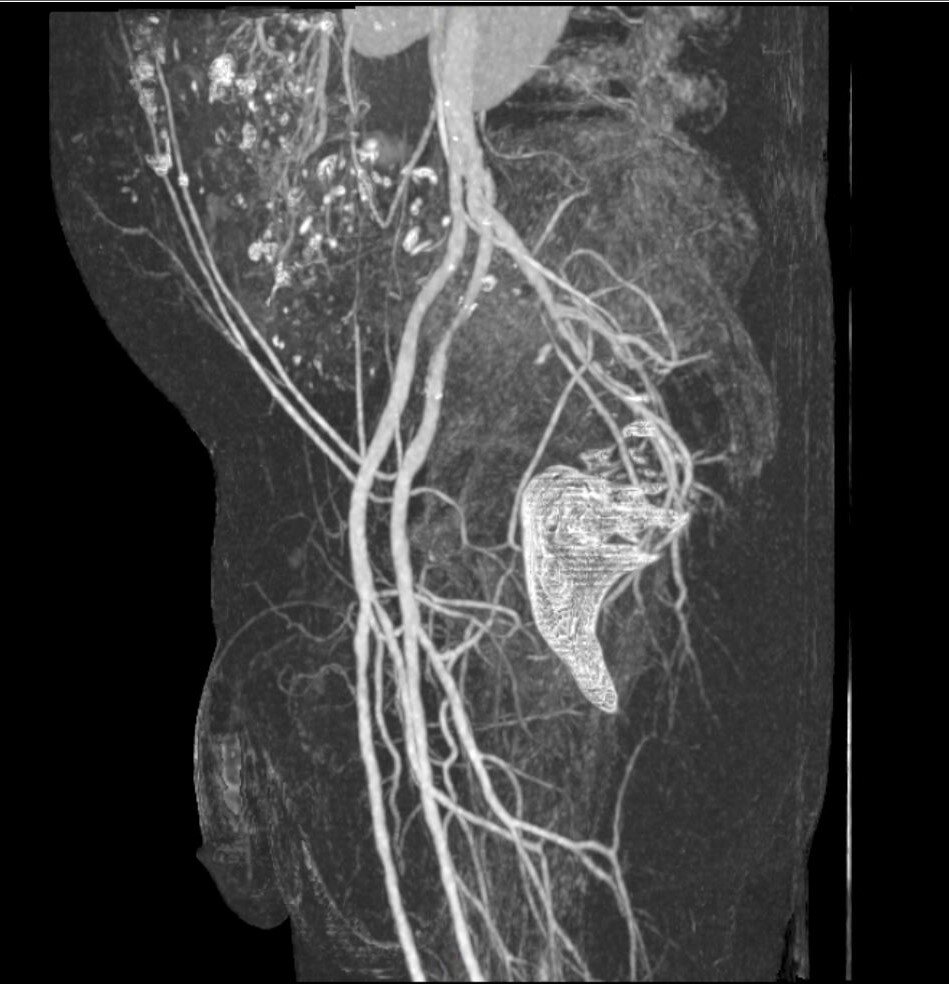

Dreidimensionale Rekonstruktion der Blutgefässe im Becken und im Penis vor der Planung einer allfälligen Therapie.